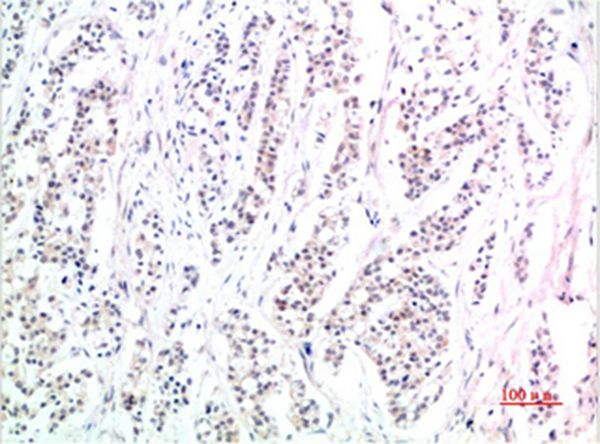

Immunohistochemical analysis of paraffin-embedded Human Skin Tissue using Phospho-Smad3(S425)Mouse mAb diluted at 1:200

Immunohistochemical analysis of paraffin-embedded Human Stomach Carcinoma Tissue using Phospho-Smad3(S425) Mouse mAb diluted at 1:200